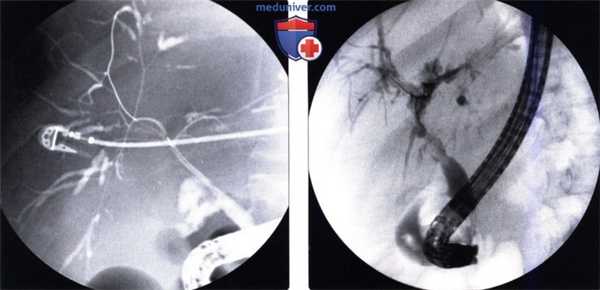

(Слева) На рентгенограмме (холангиография) у пациента, которому была выполнена трансплантация печени, с известным тромбозом печеночной артерии, определяются классические признаки ишемической холангиопатии с множественными стриктурами внутри- и внепеченочных протоков. Изменения неотличимы от таковых при первичном склерозирующем холангите.

(Справа) На рентгенограмме (холангиография) у пациента с выраженным стенозом печеночной артерии, которому была выполнена трансплантация печени, определяется диффузная деформация билиарного дерева с наличием стриктур — изменения, обусловленные ишемической холангиопатией.